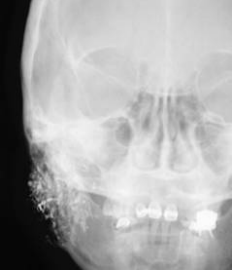

55. 承上題,下圖為病人之Waters’view X光檢查,下列敘述何者正確(箭頭表骨折處)? (A)兩側顴骨骨折 (B)勒福氏一型骨折 (C)勒福氏二型骨折合併左側顴骨骨折 (D)勒福氏三型骨折合併左側顴骨骨折

56.承上題,這位患者在當天接受緊急手術,下列為患者所接受之處置,其順序何者為適當? ①Intraoral approach over vestibular area ②Locate the fracture sites ③Arch bar splinting and intermaxillary fixation ④Miniplate and mini screws fixation ⑤Check the occlusion and close the wound (A)③→②→④→①→⑤ (B)①→②→③→④→⑤ (C)②→①→③→④→⑤ (D)③→①→②→④→⑤